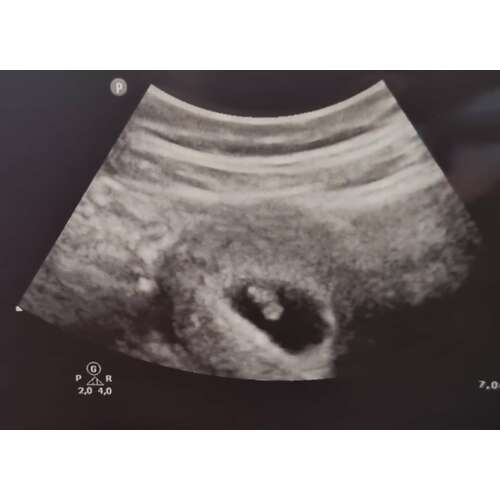

Bij mij was mijn vruchtzakje ook helemaal niet mooi rond. De gynaecoloog heeft hier ook nooit iets van gezegd. Intussen is ze al bijna 5 maandjes oud🥰

Als ik naar al mij 4 keer de zwangerschappen en echo's heb gekeken rond de 6 weken was het bij mij ook allemaal hobbelig en niet mooi rond. 1 van alle is esn miskraam geworden maar dat konden ze niet zien aan de vorm ik heb het ook echt nog nooit gehoord... de volgende echo's werden ze al wat mooier rond... maar hun hebben ervoor gestudeerd... wanneer mag je terug?

Hoi allen, hoe is het uiteindelijk bij jullie allemaal verlopen? Wij hadden gister onze eerste echo (ongeveer 6.3 wk) en onze Vk was ook wat voorzichtig met goed nieuws brengen door de vorm van de vruchtzak. Echter wel een hartslag; langzaam maar dit hoeft nog niets te betekenen met dit termijn.

Ik heb tijdens bloedverlies twee echo's gehad met een kloppend hartje. Veel stolsels ook om de vruchtzak heen in mijn baarmoeder.

Vier dagen later op de echo geen kloppend hartje meer en de vk zei toen nog dat de vruchtzak er ook niet mooi rond meer uit zag. Dus bij mij was dat helaas geen goed teken.